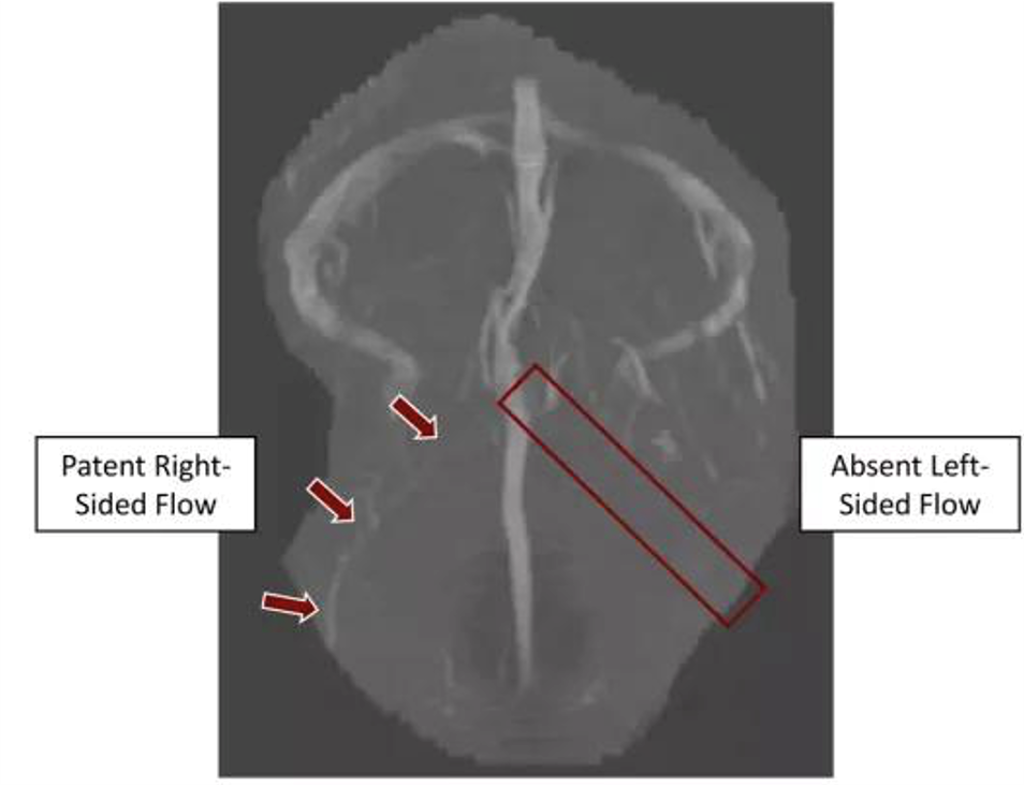

CT VENOGRAM:

FILLING DEFECT OF SUPERIOR SAGITTAL SINUS, EXTENDING BILATERALLY INTO THE TRANSVERSE SINUSES AND VEINS OF TROLLARD. EMPTY DELTA SIGN IS SEEN.